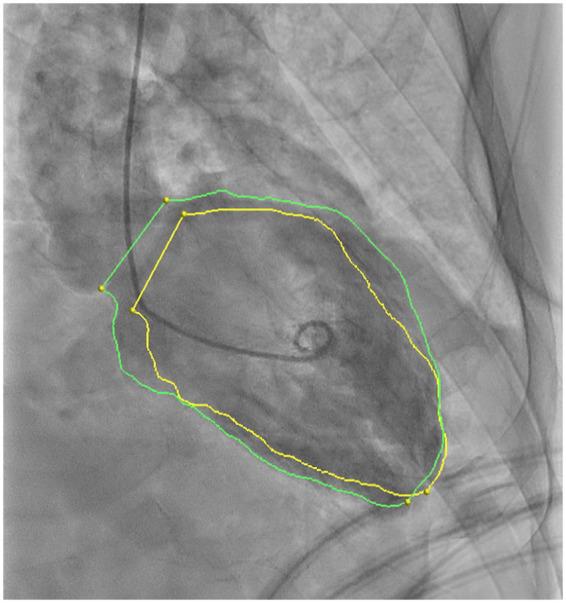

This case deals with a 69-year-old gentleman on second-line therapy with pembrolizumab for advanced non-small cell lung cancer. Three weeks after first dose, the patient was diagnosed with an autoimmune hepatitis, treated with decreasing corticoid dosage, followed by acute heart failure. On admission, his electrocardiogram (ECG) showed diffuse repolarization changes and a transthoracic echocardiography revealed severe left ventricle impairment (left ventricular ejection fraction 32%). High-sensitivity cardiac troponin was elevated and a coronary angiogram was performed showing non-significant obstructive disease. An autoimmune myocarditis was suspected, and high-dose intravenous corticoid, intravenous vasodilators, and loop diuretics were started with favourable response. Cardiac magnetic resonance (CMR) imaging, performed 2 weeks after clinical onset, revealed extracellular oedema in the anteroseptal-apical left ventricle segments. A new transthoracic echocardiography, performed after 3 months, showed preserved left ventricle ejection fraction. Finally, the patient was readmitted due to an autoimmune myasthenia-like syndrome.

本病例涉及一名69岁男性,接受帕博利珠单抗二线治疗晚期非小细胞肺癌。首次用药三周后,患者被诊断为自身免疫性肝炎,接受了逐渐减量的皮质类固醇治疗,随后出现急性心力衰竭。入院时,他的心电图(ECG)显示弥漫性复极改变,经胸超声心动图显示严重左心室功能损害(左心室射血分数32%)。高敏心肌肌钙蛋白升高,冠状动脉造影显示无明显阻塞性病变。怀疑为自身免疫性心肌炎,开始使用大剂量静脉皮质类固醇、静脉血管扩张剂和袢利尿剂,反应良好。临床发病两周后进行的心脏磁共振(CMR)成像显示左心室前间隔-心尖段细胞外水肿。三个月后进行的新的经胸超声心动图显示左心室射血分数恢复正常。最后,患者因自身免疫性重症肌无力样综合征再次入院。